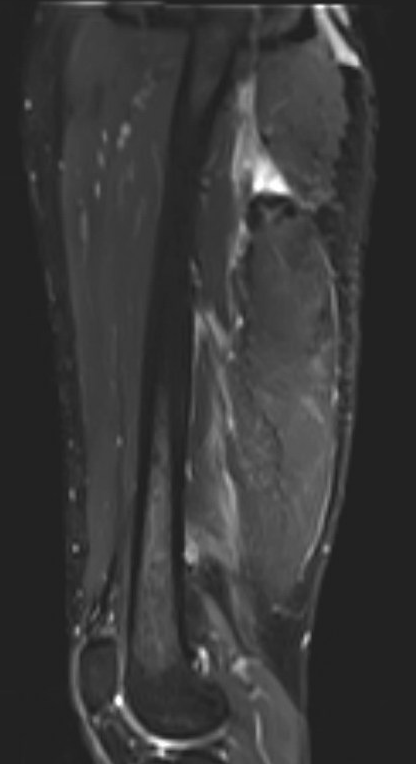

Proximal hamstring avulsion, with tendon floating in hematoma / seroma